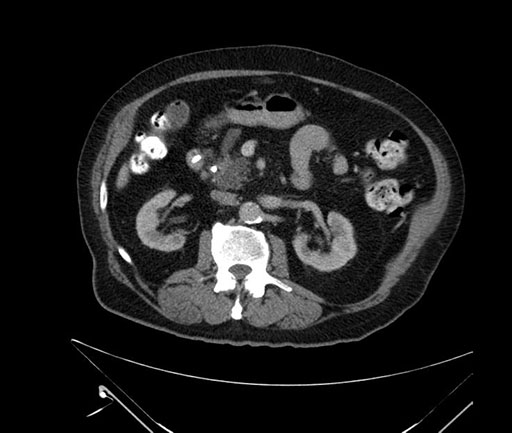

Whipple (pancreaticoduodenectomy) [case 7]

Imaging Analysis

Look through the patient's CT scan to identify any areas of concern for the necessary procedure.

Axial - stented